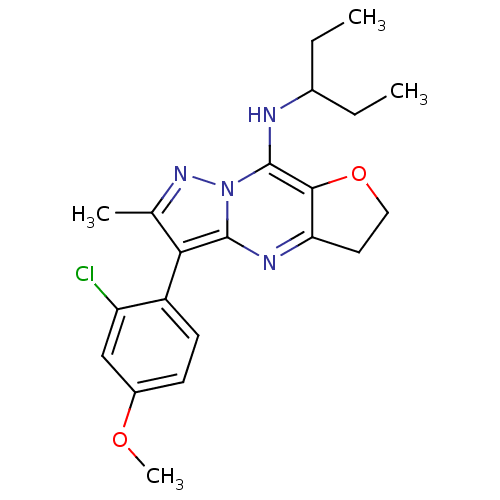

TargetCorticotropin-releasing factor receptor 1(Homo sapiens (Human))

Dupont Pharmaceuticals

Curated by ChEMBL

Dupont Pharmaceuticals

Curated by ChEMBL

Affinity DataEC50: 0.700nMAssay Description:Antagonist activity at human CRF1 receptor expressed in CHO-K1 cells assessed as inhibition of CRF-induced cAMP accumulation after 15 mins by cAMP en...More data for this Ligand-Target Pair